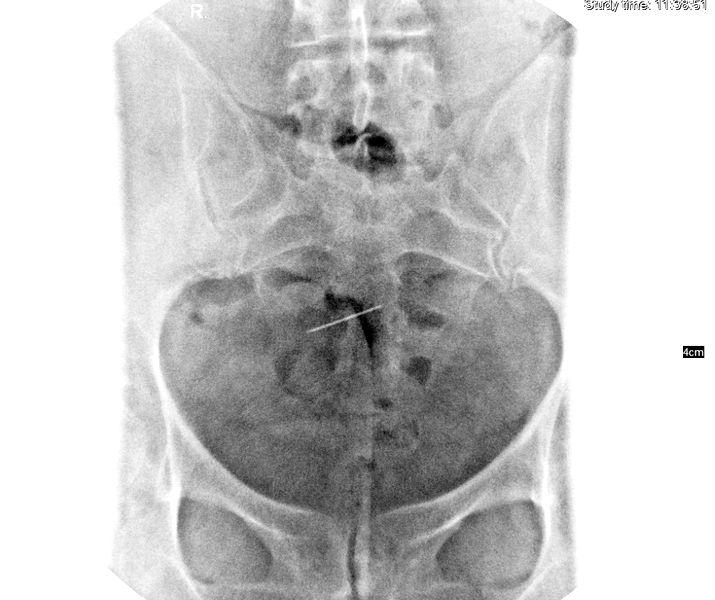

Radiografie

În răspunsul primit de la Colegiul Medicilor se precizează că – în timpul intervențiilor chirurgicale – nu se folosesc ace drepte, ci numai ace curbe. „În timpul intervenţiilor noastre din sfera pelvină nu se folosesc ace drepte, ci numai ace curbe, nici nu am avut vreodată în spital ace drepte pentru sutură. În concluzie, este dificil de a face legătură cauzală între imaginea radiologică prezentată în copie xerox, simptomele declarate de sesizantă şi operaţia care a avut loc cu 23 de ani în urmă“, se menţiona atunci în răspunsul oferit de Colegiul Medicilor Iaşi.